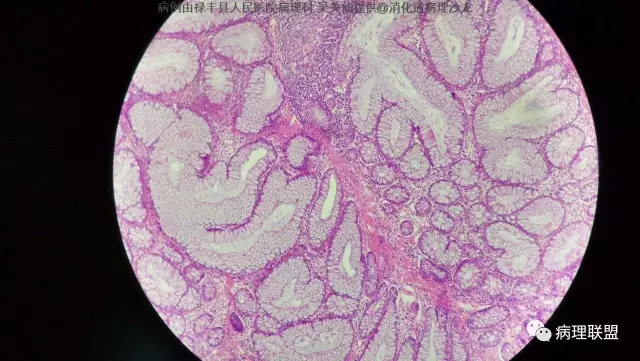

M/50 直肠(P-J息肉VS增生性息肉?)

P-J息肉?增生性息肉?请老师们看看!(病例由禄丰县人民医院病理科 吴美仙提供,致谢!)